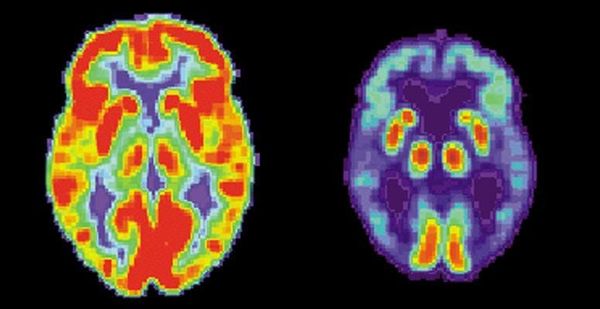

Results released on the October 8th revealed that scientists are making promising progress in the development of an effective malaria vaccine called RTS,S. The vaccine could potentially save millions of lives as it aims to combat one of the world’s deadliest diseases. This mosquito-borne disease kills approximately 660,000 people a year, mostly children, and almost all in Africa. The nature of malaria makes it extremely hard to vaccinate against: it is caused by protozoal parasites,which are considerably larger and more complex than bacteria and viruses. These unwieldy organisms are capable of wearing a number of different protein coats to disguise themselves from the immune system, making them exceptionally difficult to detect. It is thus essential for the vaccine to protect against something permanent on the surface of the parasite. The imminent vaccine aims to defend against Plasmodium falciparum, currently the deadliest strain of malarial parasite. P. falciparum, which like many other protozoal parasites, follows a specific lifestyle once inside the body. Injected through the bite of a female anopheles mosquito, the parasite enters the bloodstream and is carried straight to the liver to infect liver cells. At this stage of its lifecycle it is called a sporozoite and expresses a surface protein called a circumsporozoite. Researchers are using this circumsporozoite molecule to act as part of the immunization. It will be this molecule that the immune cells become sensitive to and seek to destroy when next detected within the body. Unfortunately for researchers, circumsporozoites alone are not enough to provoke a sufficient immune response. They must be combined with another antigen to do so. The vaccine in question creates a hybrid of circumsporozoite antigens with Hepatitis B surface antigens and an additional immune booster. It is this combination that prompts the necessary immune reaction. Trials so far have been promising. The recently released results indicated that young children (aged 5-17 months at the beginning of the trial) experienced 46% fewer cases of malaria than those immunised with a control vaccine. Infants (aged 6-12 weeks at the beginning of the trial) were reported to experience 27% fewer cases of malaria. Initially designed in 1987, it has been a long time in the making. It is hoped that it will be available for use by 2016. Whilst not providing complete protection, the sheer number of people suffering and dying from malaria worldwide, estimated at over 300 million cases, means this is a huge step forward.